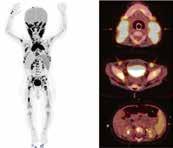

Resultater

Vi fikk svar fra 16/19 (84%) land (tabell 1). Ni av responden tene var kvinner, og 13 av 16 hadde over 10 års erfaring med nyfødtmedisin. Den anbefalte nedre grense for resuscitering av EPB i ulike land varierte fra uke 22 til uke 24 (tabell 1). De tre viktigste faktorene ved vurderinger om å frastå fra å starte intensivbehandling var foreldrenes ønsker, gestasjons alder og risiko for alvorlig senskade, mens kostnader, kjønn og flerlinger var de minst viktige faktorer (Figur 2).

De viktigste faktorene ved vurderinger om å trekke tilbake intensivbehandling var risiko for alvorlige senskade, etter fulgt av fremtidig livskvalitet og foreldrenes ønsker, mens kostnader var den minst viktige faktoren (Figur 3). Ifølge alle respondentene ble både det å frastå fra og tilbaketrekking av intensivbehandling tatt i samråd mellom lege og foreldre,

men der legens innflytelse var større enn foreldrenes, spesielt ved avgjørelser om tilbaketrekking av behandling (Figur 4).